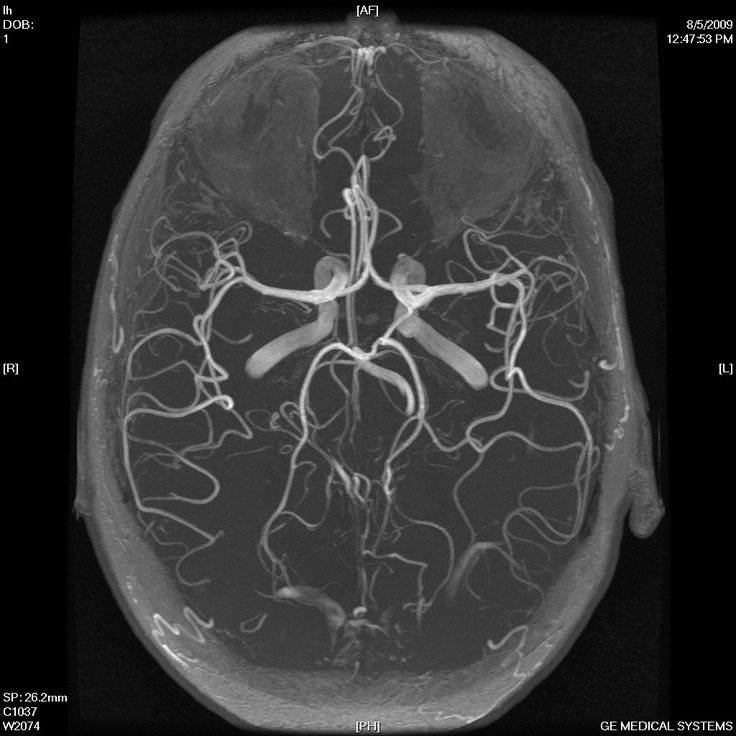

V znanstveni reviji Proceedings of the National Academy of Sciences je bila nedavno objavljena britansko-nizozemska študija, v kateri so se znanstveniki spraševali, kako se izogniti nevrološkim posledicam, ki pogosto sledijo pretresu možganov. Prvotnim znakom, kot so bruhanje, glavobol in izguba zavesti, v najbolj črnem scenariju sledijo hujše težave - otekanje možganov, možganske krvavitve, motnje vedenja in spomina ter epileptični napadi.

Pretres možganov je pogosta poškodba pri tistih, ki se ukvarjajo s kontaktnimi športi, kot sta rugby ali boks, ali pa so samo nekoliko bolj nerodni. Po močnem udarcu v glavo pride do poškodbe možganskih celic in žilic, zato se na tem mestu razvije vnetje, pri katerem glavno vlogo odigra kompleks membranskega napada. To je del prirojenega imunskega sistema, ki brez pomoči protiteles prepozna in odstrani poškodovane celice.

Raziskovalna skupina je tekom raziskave razvila protein, ki se hitro in specifično veže ravno na omenjeni kompleks membranskega napada, ki je prisoten na mestu poškodbe. Njegova količina se je po dodatku proteina v možgane mišk zmanjšala, verjetnost naknadnih nevroloških zapletov pa je upadla za kar 50 odstotkov. Ukrep je bil izveden od pol ure do štirih ur po poškodbi, kar nakazuje na potencialno rabo v urgentni medicini.

Pretirana ograjenost od okolice lahko pogosto vodi v kopičenje problemov. Podobno velja tudi za človeške možgane, ki so obdani s krvno–možgansko pregrado. Kljub njeni zaščitni vlogi, predstavlja ta glavno oviro v dostavljanju zdravil do možganov. Zdravljenje možganskih tumorjev, Alzheimerja in drugih bolezni je zato izredno težko, saj številna zdravila ne morejo preiti pregrade.

Preboj v dostavi zdravil preko krvno-možganske bariere je dosegla kanadska skupina raziskovalcev pod vodstvom doktorja Mainprizea. To so dosegli s pomočjo zračnih mehurčkov, vbrizganih v kri bolnice. Ko so ti pripotovali do možganov, so jih raziskovalci obstreljevali z ultrazvokom, zaradi česar so se mehurčki začeli raztezati in krčiti.

Zaradi pulziranja mehurčkov so se na krvno–možganski pregradi ustvarile majhne rane, oziroma luknje, skozi katere so nato lahko prehajala zdravila. Nastale luknjice so bile tudi zadosti majhne, da so se poškodbe zacelile po dvanajstih urah. Metoda se je skratka že izkazala za uspešno.

Če bo metoda prišla v redno uporabo, se obetajo številne nove možnosti za zdravljenje možganskih bolezni, ki jih do sedaj z zdravili ni bil mogoče ciljati.